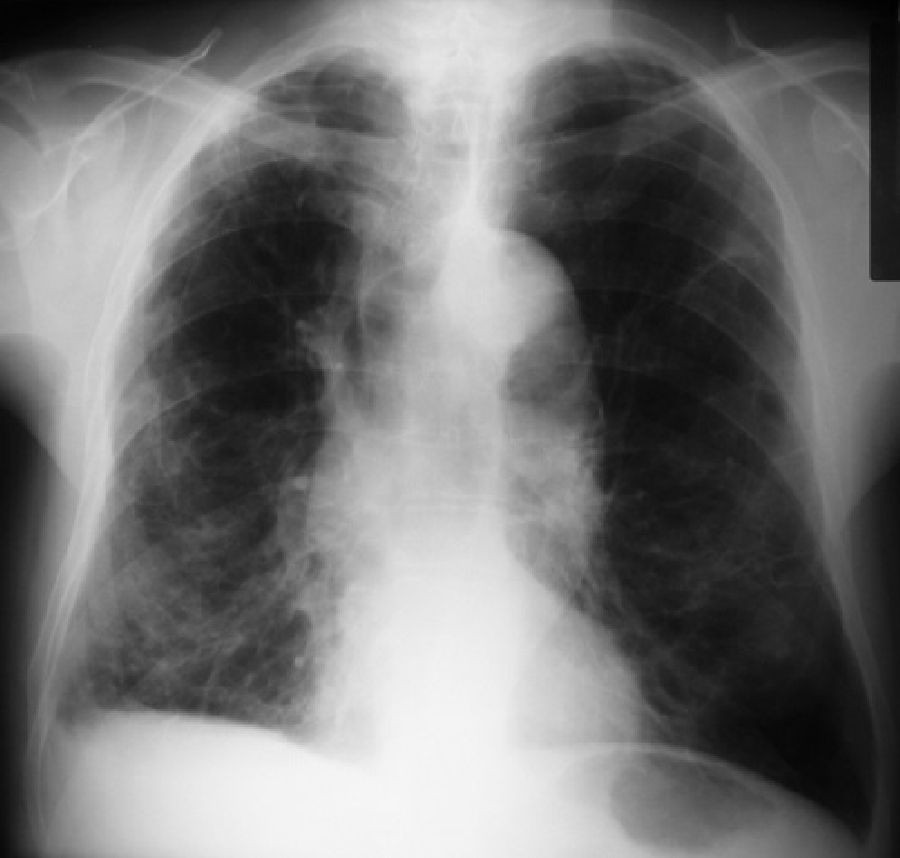

"Este trabajo, derivado del análisis cuidadoso de imágenes pulmonares de pacientes con EPOC, muestra que un desarrollo pulmonar anormal puede representar una gran proporción del riesgo de EPOC entre los adultos mayores --señala James Kiley, director de la División de NHLBI de Enfermedades pulmonares--. Se necesita más investigación para comprender qué impulsa este hecho y para idear posibles intervenciones".

Para averiguar si las vías respiratorias pequeñas podrían ser las culpables de la EPOC en personas que no fumaban o que tenían otros factores de riesgo, un equipo dirigido por Smith examinó los registros de más de 6.500 adultos mayores que participaron en tres estudios que incluyeron a fumadores y no fumadores con y sin EPOC.

Cada estudio, el Estudio Multiétnico de Aterosclerosis (MESA), el Estudio de los Pulmones, el Estudio de Subpoblaciones y Medidas de Resultados Intermedios en la EPOC (SPIROMICS) y el estudio de la Cohorte Canadiense de Enfermedad Pulmonar Obstructiva (CanCOLD), evaluaron la disanapsis usando tomografías computarizadas (CT) de los pulmones.

En los estudios MESA Lung y CanCOLD, los participantes con vías aéreas más pequeñas en relación con el tamaño del pulmón tenían muchas más probabilidades de desarrollar EPOC en comparación con aquellos con las vías respiratorias más grandes en relación con el tamaño del pulmón. La asociación se mantuvo después de considerar los factores de riesgo de EPOC estándar, incluidos el tabaquismo, los contaminantes y el asma.

Luego, los investigadores se centraron en los participantes del estudio CanCOLD que nunca fumaron y los fumadores empedernidos del estudio SPIROMICS. Nunca los fumadores con EPOC tenían vías respiratorias mucho más pequeñas en relación con el tamaño del pulmón, mientras que los grandes fumadores que no tenían EPOC tenían vías respiratorias más grandes de lo normal.